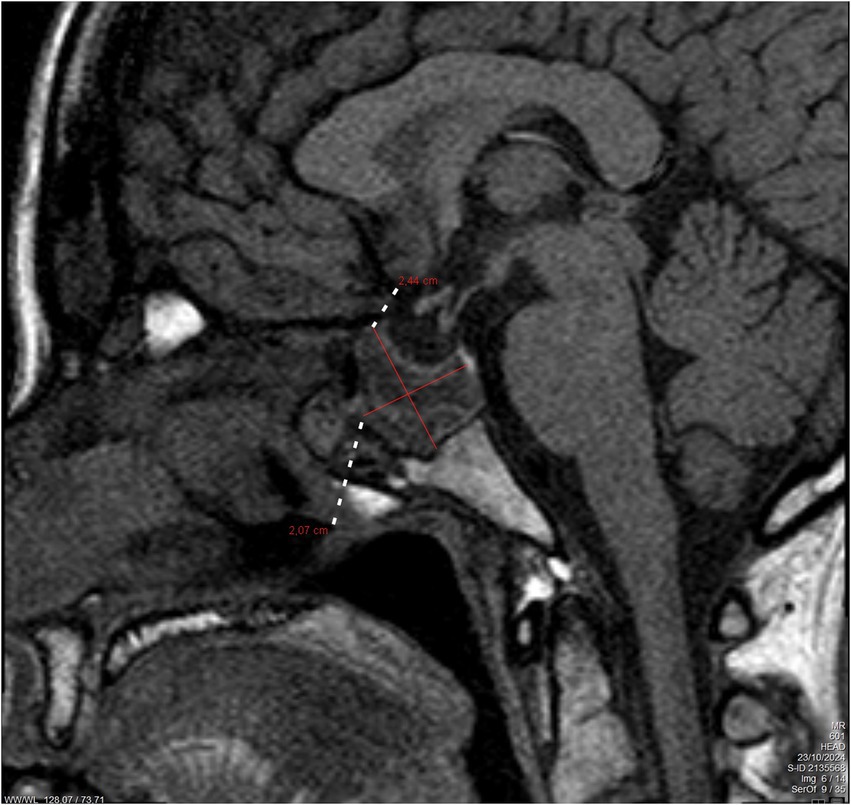

Background: Prolactinomas are the most common functional pituitary adenomas and may lead to infertility, visual field defects, and neurological impairment. Pregnancy poses unique challenges in women with macroprolactinomas due to the potential for tumor enlargement under the influence of gestational hormonal changes. Case: We present the case of a 40-year-old woman who conceived through in vitro fertilization (IVF) and presented at 38 + 3 weeks of gestation with new-onset diplopia. Magnetic Resonance Imaging (MRI) revealed a 29 mm hemorrhagic macroprolactinoma causing compression of the optic chiasm. The tumor had been previously asymptomatic and untreated. Management was undertaken by a multidisciplinary team including obstetricians, endocrinologists, neurosurgeons, and anesthesiologists. An elective caesarean section was performed under general anesthesia with careful attention to intracranial pressure control and hemodynamic stability. Outcome: Delivery was uneventful, with no perioperative neurological or anesthetic complications. The patient was discharged in good general condition and commenced on long-term dopamine agonist therapy, with planned close endocrinological and neurosurgical follow-up. Conclusion: This case highlights the importance of early diagnosis, individualized management, and multidisciplinary coordination in pregnant women with macroprolactinomas. Dopamine agonists remain the cornerstone of therapy and are generally safe during early pregnancy. Meticulous anesthetic planning is essential to optimize maternal and fetal outcomes.